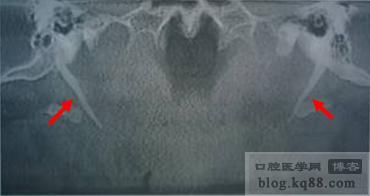

圖10常規(guī)曲面體層片

圖10